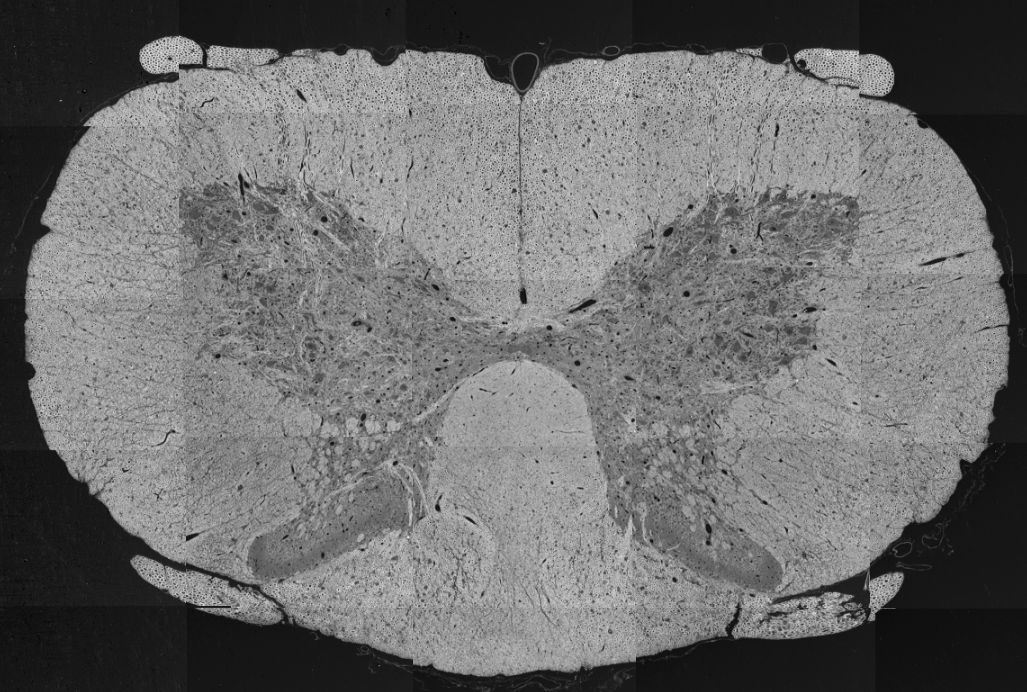

Below is an example of a spinal cord SEM overview, modified from Zaimi et al., 2018. doi:10.1038/s41598-018-22181-4.

sub-01_sample-01_photo.jpg